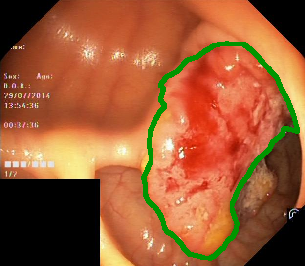

Figure 1: Polyp visual aspects have a wide variety in terms of shape and color. Four different polyps sampled from the different databases considered in this work: (a) Kvasir-Seg [19], (b) CVC-ClinicDB [5], (c) CVC-ColonDB [4], (d) ETIS [29].

The large bowel within the human gastrointestinal tract can be affected by different diseases, among which, Colorectal Cancer (CRC) is particularly concerning. CRC represents the second most common cancer type in women and third most common for men [15]. Gastro-intestinal polyps are known precursors of this type of cancer [34], being present in almost half of the patients over 50 undergoing screening colonoscopies [31]. This kind of lesions show a wide range of shapes and visual appearances, as shown in Fig. 1, turning its identification and segmentation into a challenging problem.